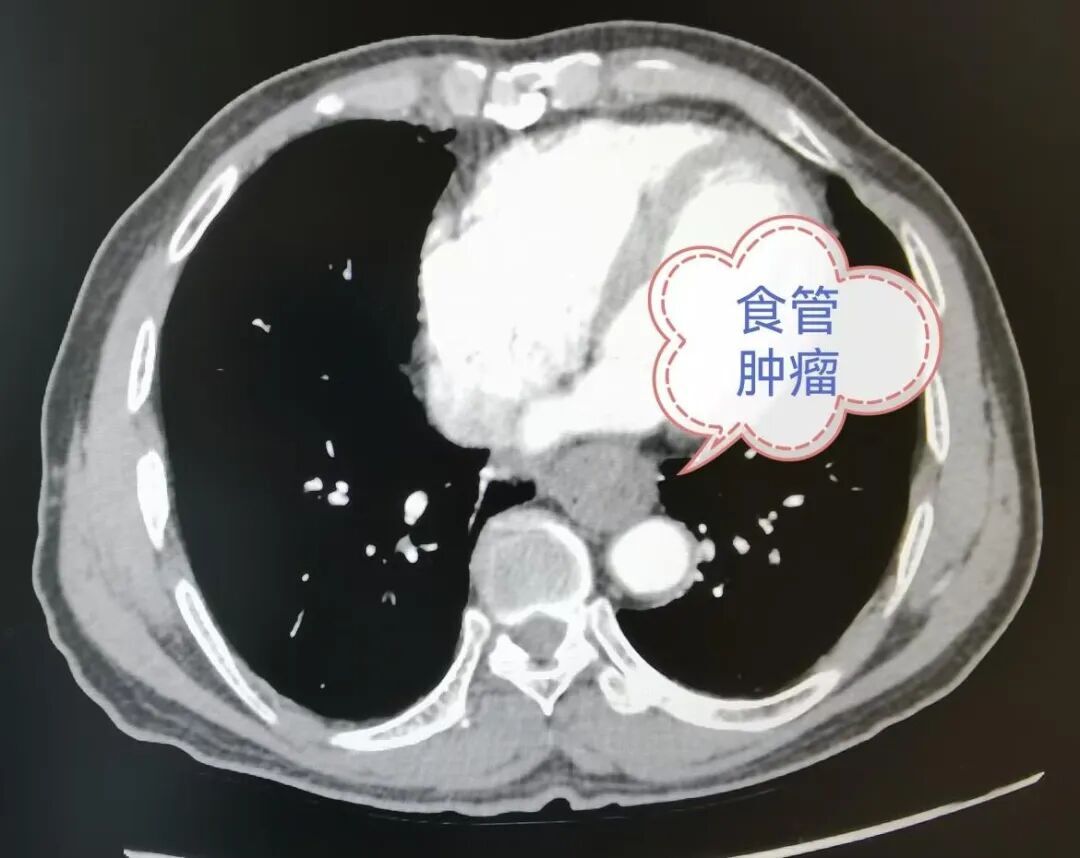

原来,数月前,吴先生频繁出现进食哽噎感,食物难以下咽,需靠喝水辅助,直到一次完全无法吞咽,才紧急来到长沙市第四医院胸外科就诊,经检查被诊断为食管癌。为吴先生完成相关检查后,胸外科邀请消化内科、普通外科二病区、医学影像科、麻醉手术科、血液肿瘤科等多学科专家会诊。专家们仔细分析检查报告,认为患者肿瘤尚未扩散,具备手术指征。

多学科团队经过缜密评估,决定采用胸腔镜联合腹腔镜的微创术式实施食管癌根治手术。手术当天,胸外科、普通外科二病区、麻醉手术科等多学科团队紧密协作,凭借丰富的经验、精湛的微创技术,顺利完成了这台高难度的食管癌根治手术。